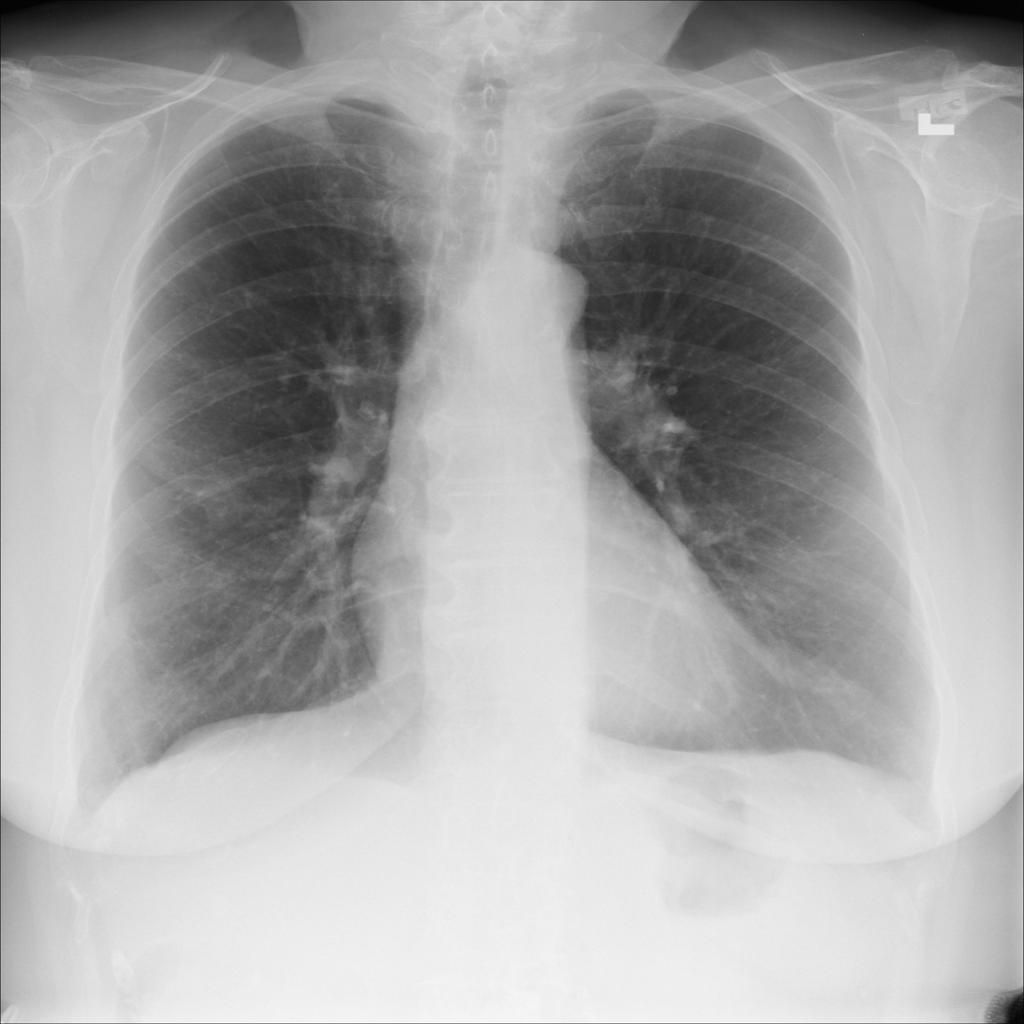

PAT-E960 · IMG-002Fibrosis

PAT-E960 · IMG-002

PA